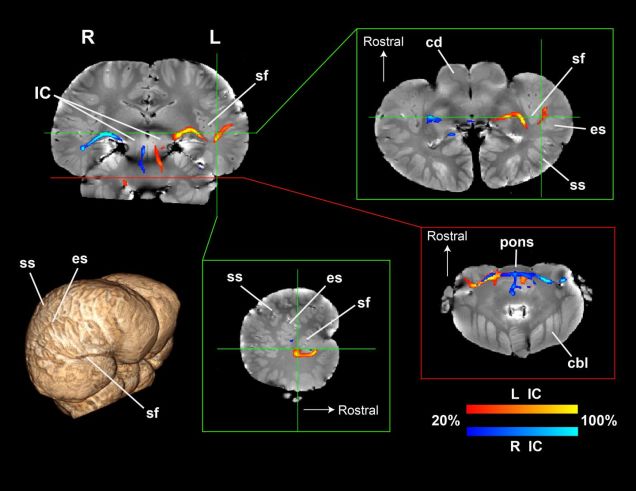

In a forthcoming paper in Proceedings of the Royal Society B, neuroscientists at Emory University have, for the first time, mapped the sensory and motor systems of two dolphin brains. Unlike most mammals, which process sound in the temporal lobe, the dolphin auditory nerve is wired to both the temporal lobe and the brain’s primary visual region. And that connection could help explain the animals’ fantastic sonar.

“For decades, we’ve thought of the dolphin brain as having one primary auditory region,” said cetacean neuroscientist and study co-author Lori Marino in a press release. “This research shows that the dolphin brain is even more complex than we realized.”